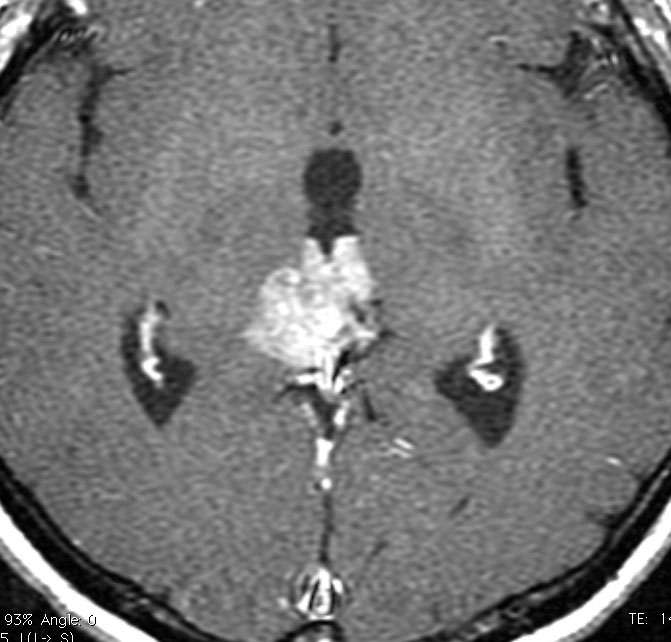

中間型松果体実質腫瘍 PPTID グレード2とグレード3の症例

中間型松果体実質腫瘍 PPTID の例1

40代男性のPPTIDグレード3です。早朝の激しい頭痛で発症しました。morning headacheは松果体腫瘍の特徴でもあります。これに対して内視鏡による第3脳室開窓術と生検術がなされてから紹介されてきました。生検術前のHCG-beta 2.1mIUと陽性でしたからgerminomaを強く疑いましたが,生検病理診断はrosette構造があり中等度の核異型を有するPPTIDであり,MIB-1 8%でした。短期間の間に増大していました。グレード3 PPTIDと判断されます。

第3脳室開窓後のCTです。左のCTでは小さな石灰化がみられます。右の造影CTでは小さなのう胞部分をのぞいて均一な増強効果がみられます。

MRIガドリニウム増強像です。腫瘍境界がわりにはっきりしていて,中脳や視床に浸潤像がありませんから,松果体芽腫ではないことが解ります。でも,この画像だけからは,松果体細胞腫やジャーミノーマとの区別はつきません。